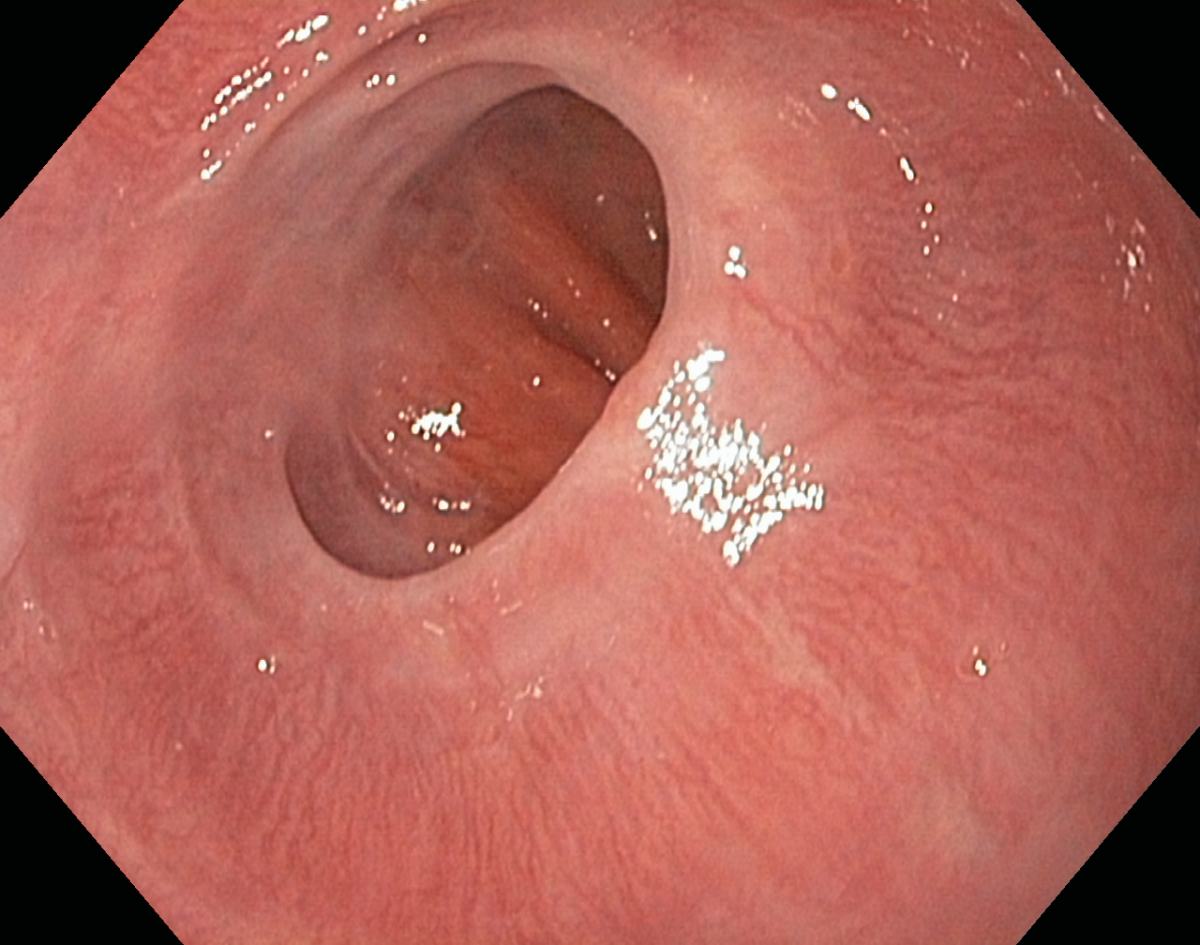

Reflux oesophagitis grade C-D according to the Los Angeles classification